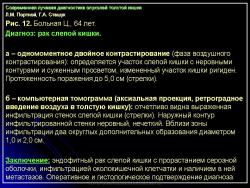

Отображение опухоли толстой кишки на компьютерных томограммах зависит от локализации процесса и характера роста. При преимущественно диффузном внутристеночно растущем раке кишки, что выявлялось гораздо чаще, при КТ отмечалось утолщение стенки кишки с неравномерным, достаточно часто циркулярным сужением просвета соответствующего участка ее, ригидностью стенки (отсутствием изменения диаметра просвета и толщины стенки при дозированном введении воздуха) и неровными внутренними контурами (рис. 11). При экзофитном характере роста опухоли при КТ внутри просвета кишки определялось дополнительное мягкотканное образование с неровными бугристыми контурами, широко прилежащее к стенке кишки. Опухоли были различной структуры: однородной, неоднородной за счет включений кальция или участков распада с наличием в опухолевой ткани жидкости и газа. При появлении газа в околокишечной клетчатке чаще всего предполагалась перфорация ее стенки. Кроме оценки состояния стенок кишки, пораженной опухолью, оцениваются и изменения в окружающих тканях и органах при распространении ее за серозную оболочку. Степень местного распространения опухоли является одним из определяющих факторов прогноза и выбора дальнейшей тактики лечения. Оценку степени распространения опухоли проводили в соответствии с Международной классификацией по системе ТNM.

При КТ слои стенки кишки не визуализируются, в связи с чем разграничить стадии Т1 и Т2 не представляется возможным. Принципиально важно с точки зрения тактики дальнейшего лечения и прогноза заболевания диагностировать прорастание серозной оболочки кишки (Т3) и смежных органов (Т4). Одним из симптомов стадии Т3 является наличие в клетчатке, окружающей кишку, тяжистых или линейных структур, распространяющихся в виде лучей от стенки измененной кишки в жировую ткань или наличия узловой структуры вблизи наружного контура пораженной опухолью стенки кишки (рис. 12).

При этом необходимо четко учитывать топографическую анатомию хода петель кишки, когда косой ход может дать эффект “дополнительного объема”. Во избежание этого желательно проведение исследования с дополнительным введением воздуха в кишку. Кроме того, достаточно трудно разграничить воспалительные изменения и отек в клетчатке, нередко сопутствующие опухоли (рис. 13).